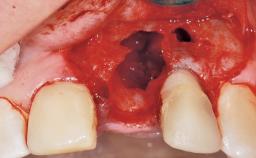

Immediate Placement of an Implant in a Maxillary Left Central Incisor Site

A 33-year-old female patient presented with an upper left central incisor that required extraction after a failed endodontic therapy. The tooth had been traumatized when the patient was a teenager and had undergone several endodontic treatments, including two apicectomy procedures. The patient was in good health and did not smoke. Clinical examination showed that the patient had a high lip line. In full smile, the gingival margins of the upper teeth were visible to the first molars. The gingival margins of central incisors 11 and 21 were only just showing. Examination of tooth 21 confirmed that the tooth was mobile and had hypererupted by 1 mm.